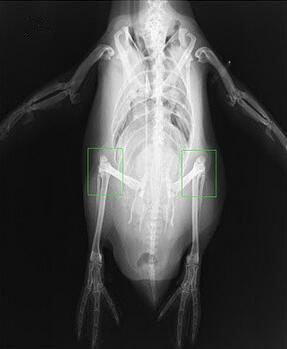

站立状态

除了好似燕尾服的皮毛,提到企鹅,通常还会想到它们萌萌的步态。在陆上行走时,行动笨拙,脚掌着地,身体直立,依靠尾巴和翅膀维持平衡。遇到紧急情况时,能够迅速卧倒,舒展两翅,在冰雪上匍匐前进;有时还可在冰雪的悬崖、斜坡上,以尾和翅掌握方向,迅速滑行。它们看上去好像没有膝盖,双腿直立,通过不断地一抬脚一放脚向前移动,一摇一摆地走着。它们的腿看起来短,但若将它们置于X光下,就可以看到它们腿的骨骼结构实际上与人腿的结构相似,由短的股骨、膝盖、胫骨和腓骨组成。之所以看上去又短又粗,是因为太胖了,厚厚的脂肪加上羽毛把大部分的腿都藏起来了。

匍匐状态

虽然有与人腿结构相似的腿部骨骼,但企鹅大半的时间都是在水中度过的,它们的骨骼进化成更适于游泳的结构。为了便于游泳,企鹅的上腿骨很短,直立的时候和地面基本平行,膝盖正好在重心正下方,看起来始终是半蹲的状态。这样的小短腿骨骼结构意味着每一步都伴随着身体重心的很大波动,如果像正常走路那样上下颠簸,那就会额外消耗能量。为此,企鹅采取了一种左右摇摆的步姿,尽力把重心变化在水平方向上解决掉。